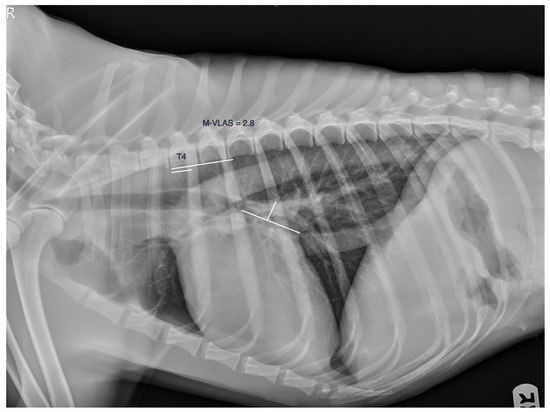

- An, S.; Hwang, G.; Noh, S.A.; Yoon, Y.; Lee, H.C.; Hwang, T.S. A Retrospective Study of Radiographic Measurements of Small Breed Dogs with Myxomatous Mitral Valve Degeneration: A New Modified Vertebral Left Atrial Size. J. Vet. Clin. 2023, 40, 31–37. [Google Scholar] [CrossRef]